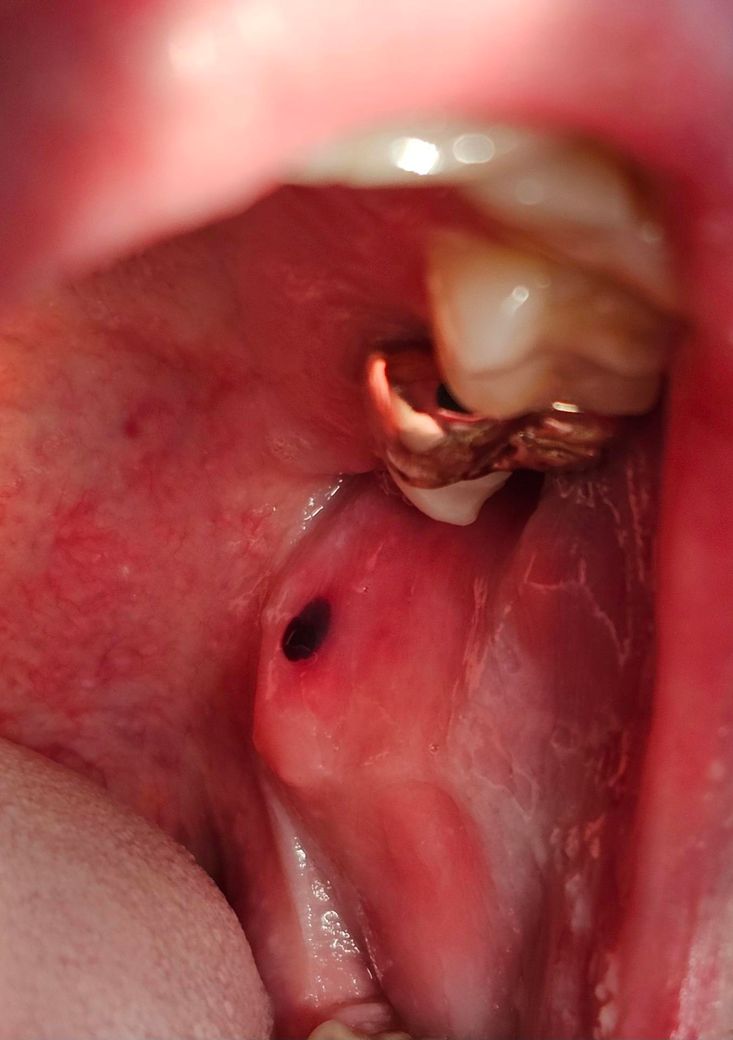

혹시 구강암일까요..?ㅠ(혐주의)

흡연은 하루 6,7개비정도 피고

10년정도 핀거같아요ㅠ

술은 한달에 1,2번 마실때 3병쯤마시구요..

혓바닥 돌리는데 작은 멍울이 느껴져서보니

이렇게 되있는데 통증은 따로 없어요

• 1번 째 사진

단순 혈종으로도 보이긴 하나, 보다 적절한 평가 시행 위해 이비인후과 내원하시면 됩니다.

관련하여 상태 평가 받아보심이 가장 중요해보입니다. 답변 도움되었기 바라며, 이비인후과 내원해주시기 바랍니다.